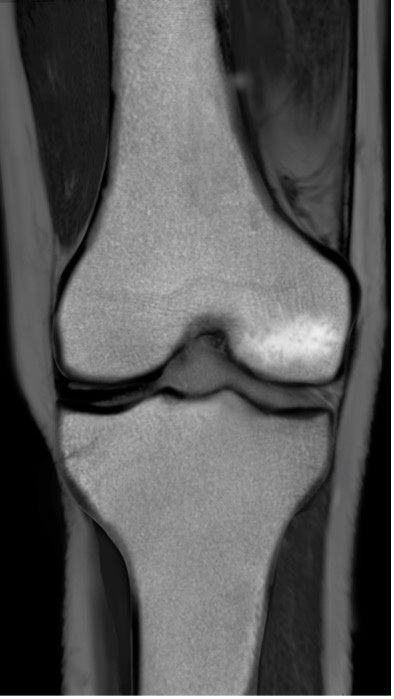

BML(Bone marrow lesion、骨髄異常陰影)はMRIで発見することのできる骨髄内の異常のことを言い、軟骨の下の骨の微小骨折による骨髄内の炎症または浮腫(水分が骨に溜まった状態)、壊死(骨が死んでしまった状態)をあらわすとされています。

BMLは痛みと強い関係があることが示されていて、標準的な保存治療のヒアルロン酸注射や近年注目されている再生医療のPRP療法でも改善しない関節痛の原因となっている可能性が指摘されています。

BMLが生じた膝関節のMRI画像